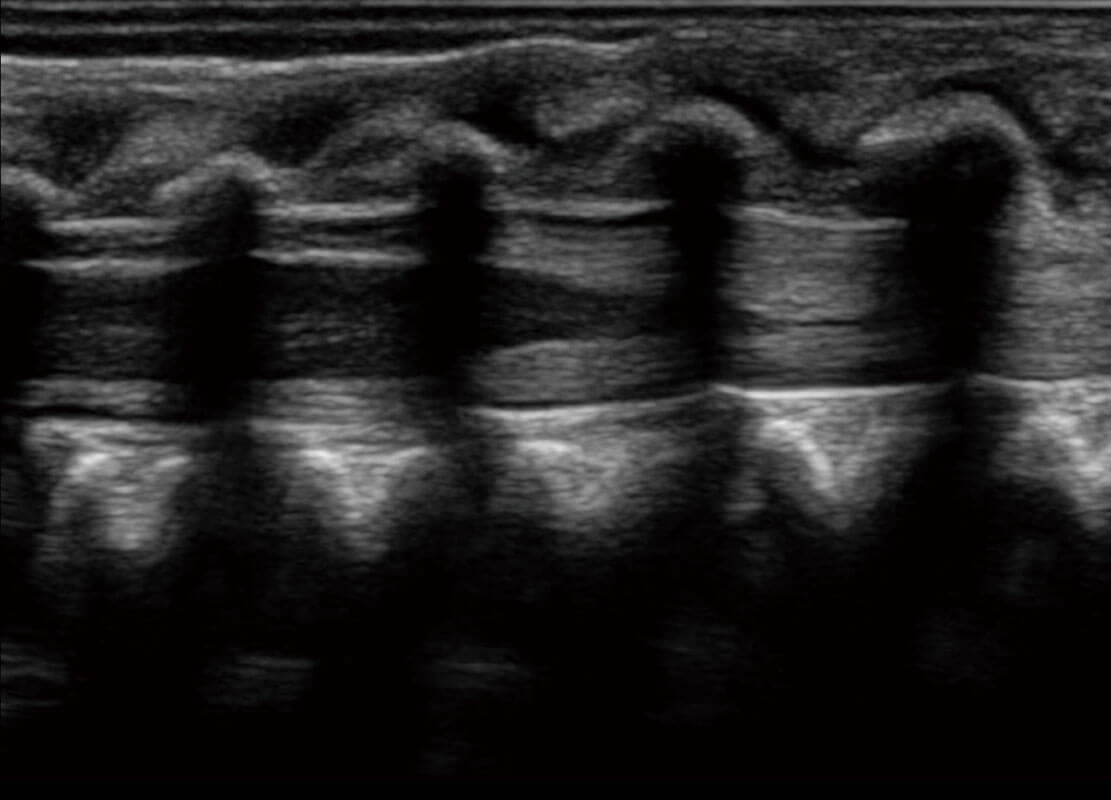

新生儿肝血管癌

新生儿脊髓圆锥

新生儿心脏